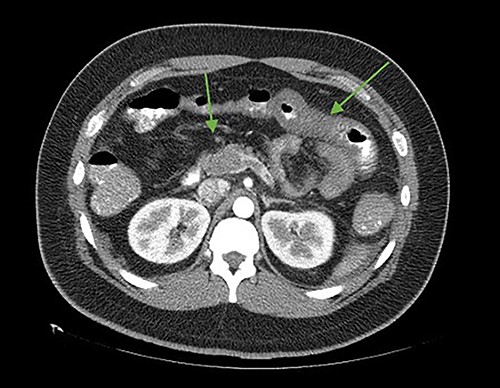

The patient was reoperated by laparoscopy, finding segmental thrombosis from 200 cm to 50 cm of the Treitz ligament, with edema and interloop free fluid without perforation (Figs 3 and 4). Lateral resection and entero–entero anastomosis were performed with manual stapler, subtracting 440 cm of intestine with adequate coloration. Later he was admitted to the Intensive Care Unit, treated with low molecular weight heparin at a full anticoagulation dose, maintaining an INR of 2 and a partial thromboplastin time of 80 s. He presented adequate evolution starting a liquid diet on the fourth postoperative day, new laboratories reported hemoglobin of 11 g/dl, 12 700 leukocytes/mm3, platelets 225 000/mcL, INR of 2. He was discharged on the fifth day with rivaroxaban treatment for 6 months.

Laparoscopic view of intestinal thrombosis 200 cm at the level of the proximal jejunum, 50 cm from the ligament of Treitz.